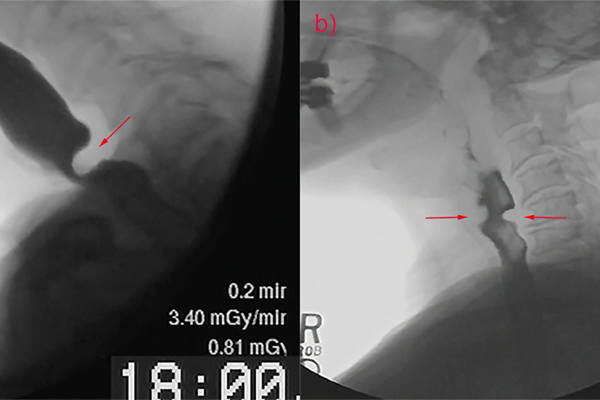

Muscle tension dysphagia: an underdiagnosed problem

Dysphagia in complex laryngology – maintaining the balance